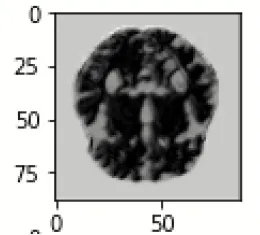

The database used in this study consists of a total of 6,200 AD images that are retrieved from the Kaggle database. It comprises grayscale images of 896 MD, 64 Mod D, 3,200 ND, and 1,966 VMD images, with a dimension of (208 × 176 × 3) pixels. The dataset for evaluation is divided in such a way that 80% of the image samples are utilized for training the model and the remaining 20% are utilized for testing the model (Filipovych et al., 2011). Figure 2 shows the database of MRI images. Table 2 shows the publicly available AD dataset.

FIGURE 2

www.frontiersin.org

Figure 2. Alzheimer's disease: (A) M.D, (B) Mod.D, (C) N.D, and (D) V.M.D.